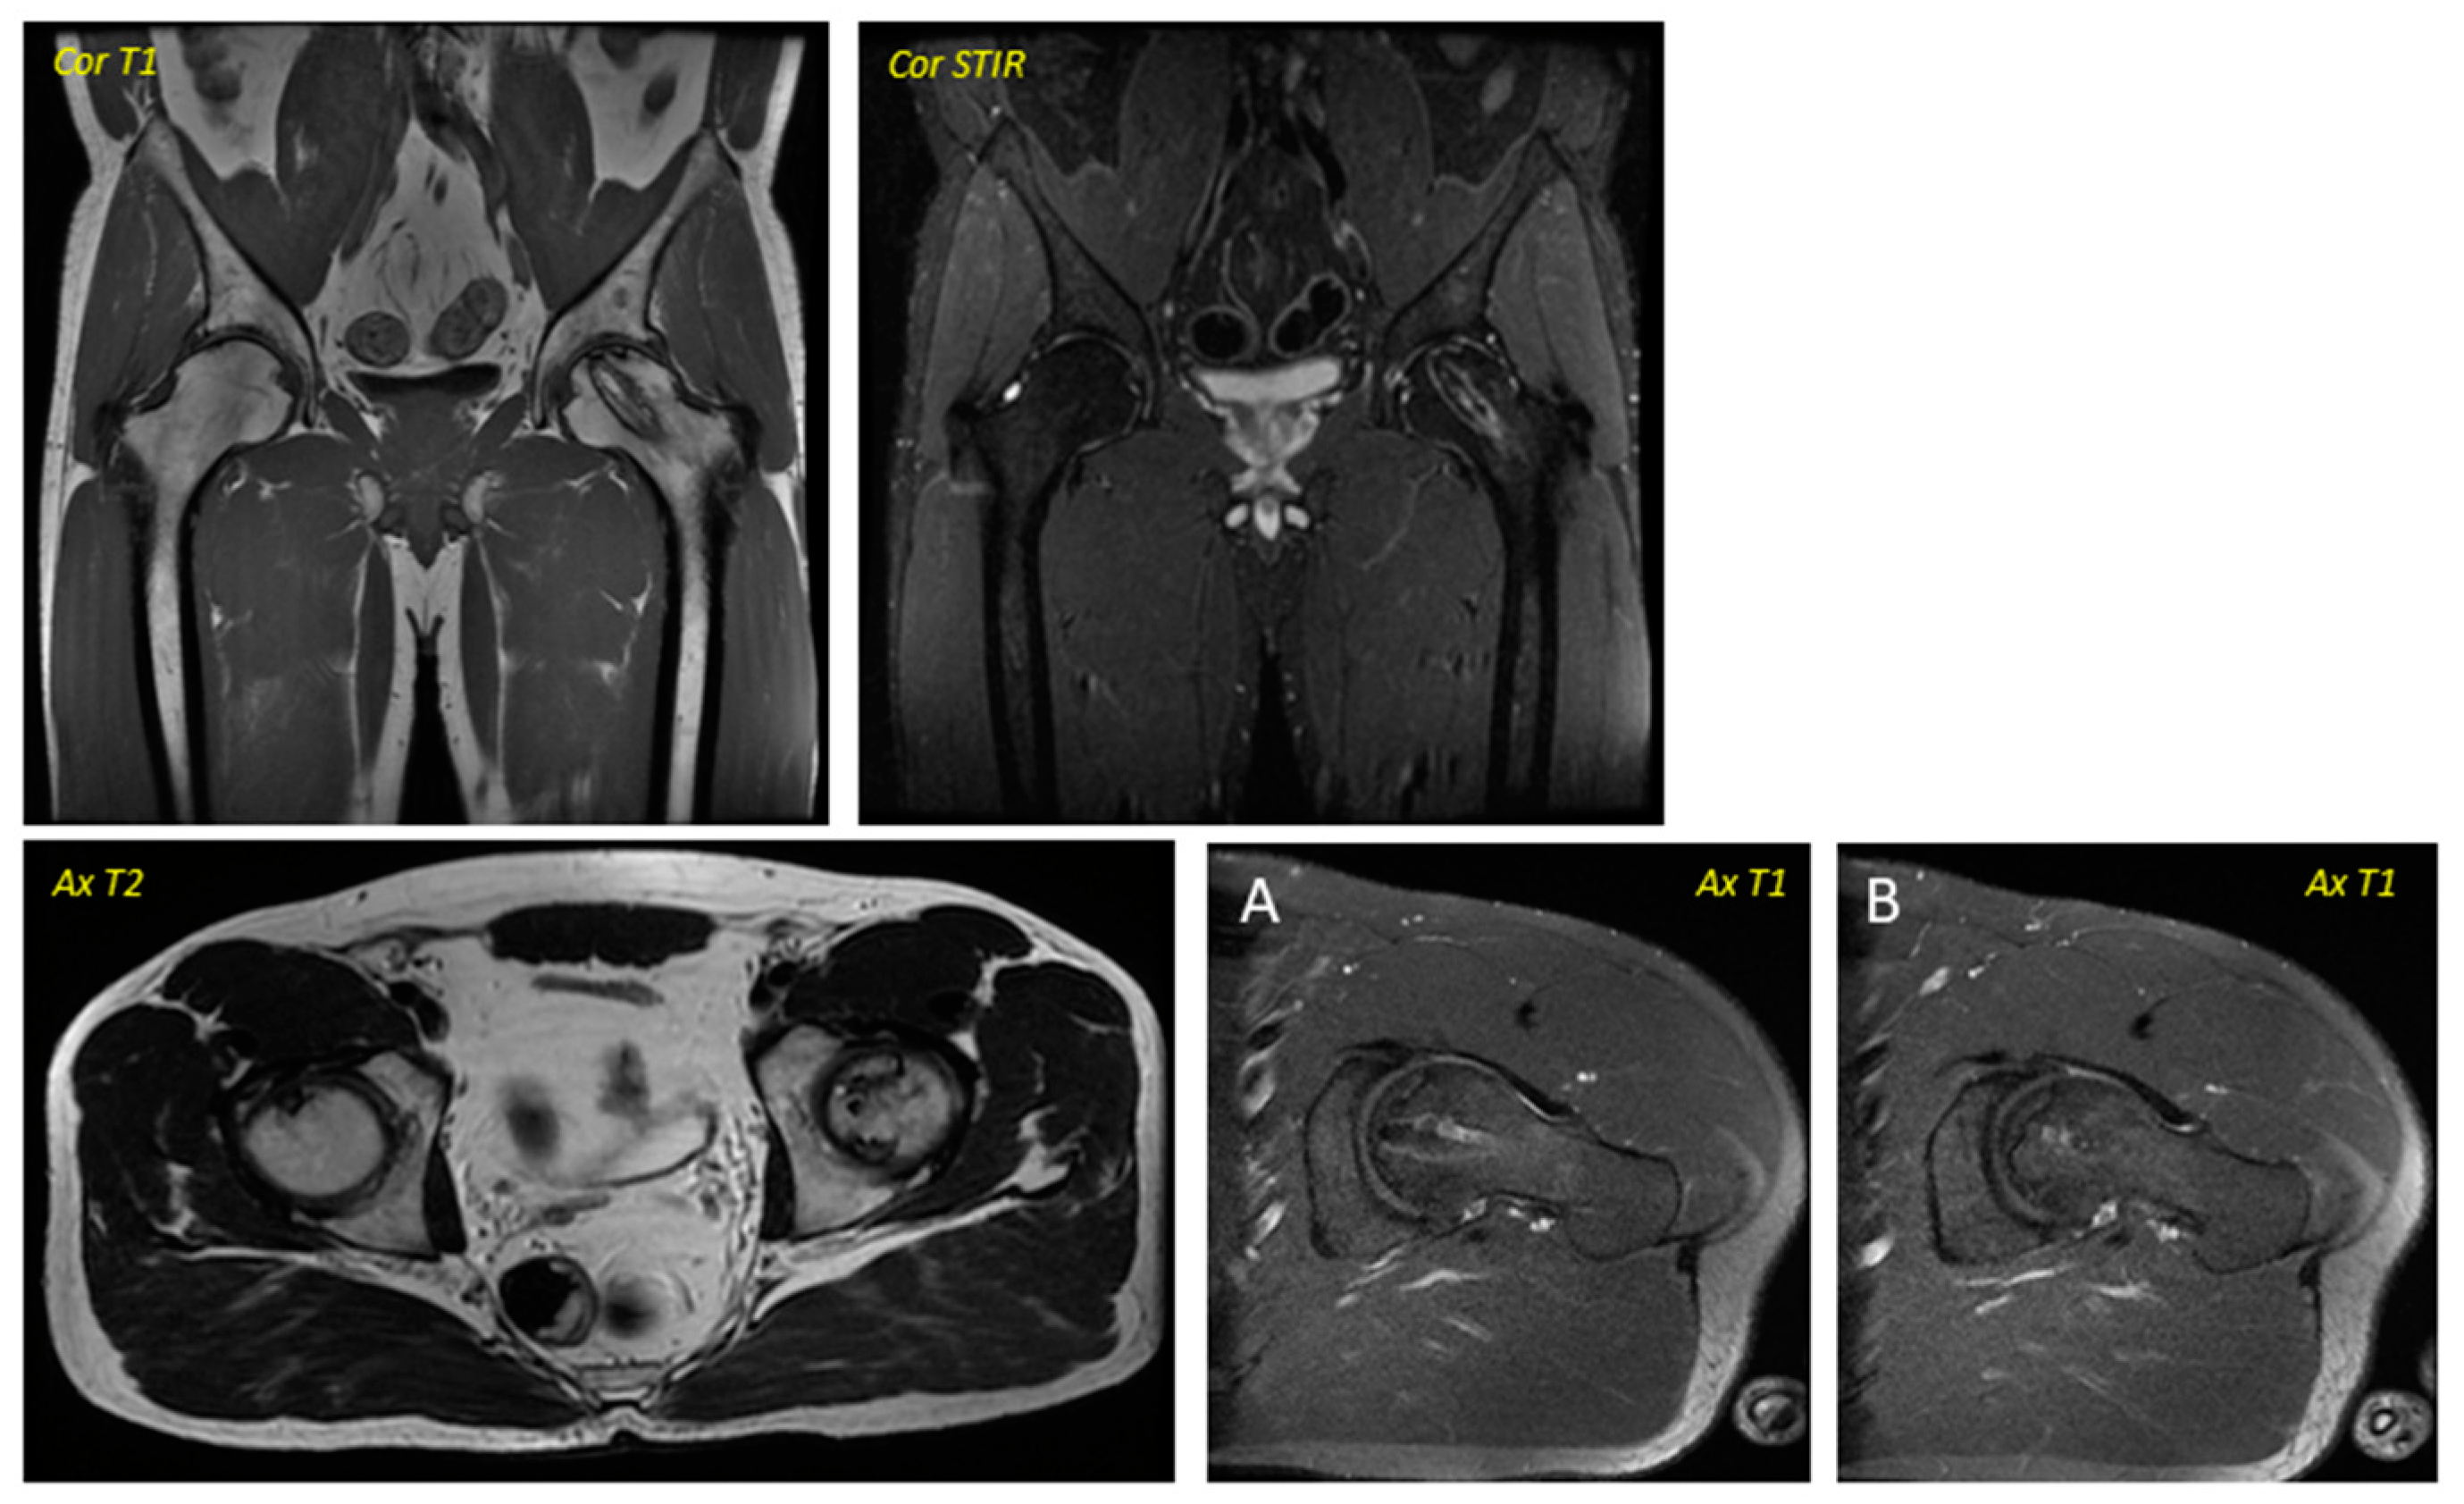

關(guān)于影像學研究,在12個月的隨訪期間,在影像學演變中觀察到了一些發(fā)現(xiàn)(圖1和圖2)。

首先,方向的變化從第六個月開始出現(xiàn)在所有病例中,而在早期階段并不明顯。其次,62.5%的患者 ( n=5) 在手術(shù)后的第一年內(nèi)實現(xiàn)了影像穩(wěn)定。第三,兩名患者 (25%) 出現(xiàn)壞死區(qū)進展,而一名 (12.5%) 患者出現(xiàn)明顯的再骨化跡象。盡管觀察到描述性差異,但后一個參數(shù)的p值在統(tǒng)計學上并不顯著。